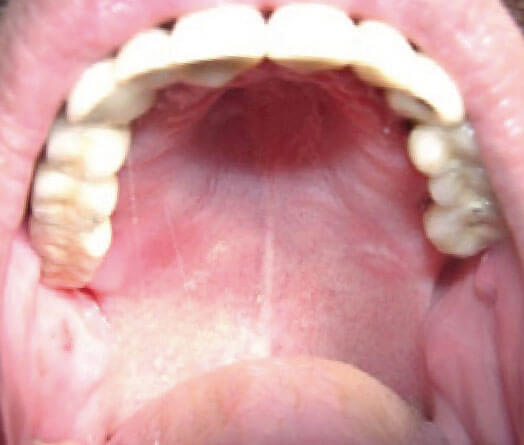

6. При большой степени атрофии альвеолярных отростков нашим пациентам мы можем предложить технологии по установке систем субпериостальных имплантатов, или экзоскелетов.

Принцип заключен в создании точной копии поверхности кости верхней и нижней челюсти. По этой копии будет моделироваться будущий экзоскелет с посадочными местами под искусственные зубы. Конструкция дополнительно крепится к кости фиксационными элементами.

Такая конструкция изготавливается индивидуально на основании данных компьютерной томографии пациента и проектируется в 3D режиме СAD/CAM инженерных приложений. Это обеспечивает высокую точность в изготовлении конструкции. Экзоскелеты могут быть изготовлены как из медицинских сплавов титана, так и из оксида циркония.